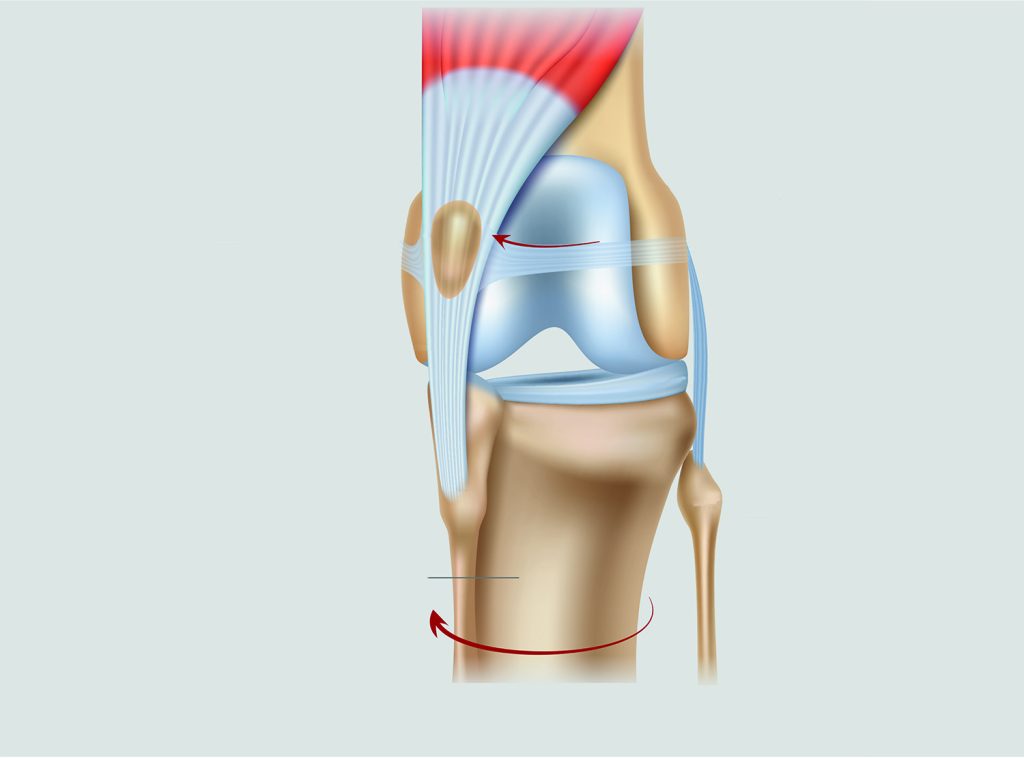

Patellaluxatie is een aandoening waarbij de knieschijf op de knie te los ligt, waardoor de knieschijf bij beweging buiten de groeve gaat. Normaal gesproken ligt de knieschrijf in de groeve van het dijbeen, de knieschijf zit via een pees vast aan een grote spier van het bovenbeen en aan de voorkant van het scheenbeen. Bij patellaluxatie schuift de knieschijf van de knie af en komt dan naast de knie te liggen.

Meestal ontstaan deze aandoening doordat er wat fout gaan in de aanleg of ontwikkeling. Genetische factoren spelen zeker een rol bij patellaluxatie. Doordat de knieschijf steeds van de knie afschiet kan het een pijnlijke aandoening zijn. In een knie met een losse knieschijf ontstaat ook sneller artrose (gewrichtsslijtage).

Er zijn verschillende gradaties van patellaluxatie. Er zijn 4 graderingen van patellaluxatie:

- Kan manueel worden geluxeerd, maar de patella schiet zelf terug in de groeve.

- Patella luxeert intermitterend, en gaat niet vanzelf terug, kan wel teruggeduwd worden.

- Patella is permanent geluxeerd en kan manueel worden teruggeduwd.

- Patella is permanent geluxeerd en kan niet manueel worden teruggeduwd.